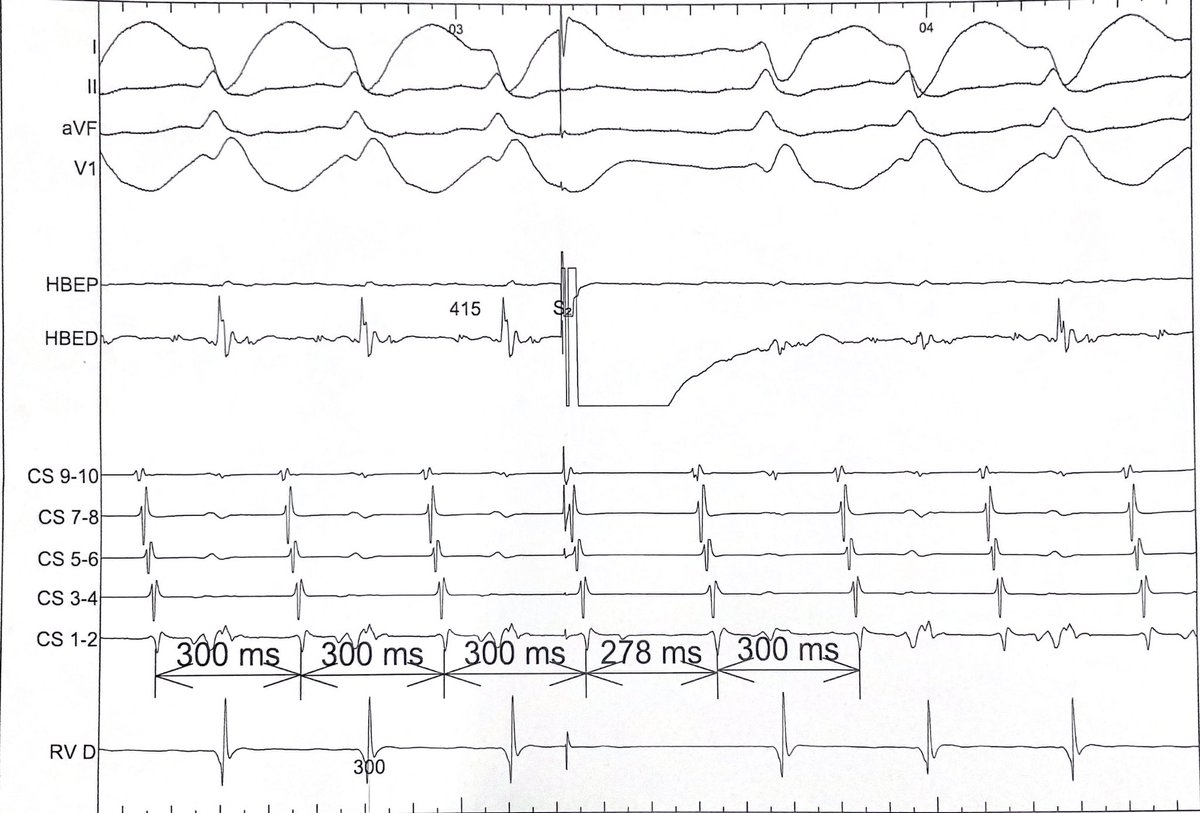

@LenSteinberg Atypical AVNRT, very early PES from His conducts Retrogradely to advance A. Selective capture of His with RV ERP. Ventricle not part of circuit.

English